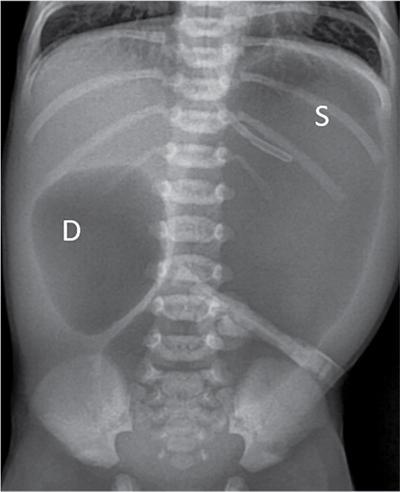

C.V. Kanimozhi, S. Muralinath, Raveendran J. Many of the important congenital gastrointestinal abnormalities present acutely in the newborn; some present much later. These include obstructive gastrointestinal lesions that present with vomiting, abdominal distension and not having passed meconium. The imaging modalities that are most commonly used in the evaluation of neonatal gastrointestinal abnormalities are plain films, contrast studies and ultrasound. Plain films remain a valuable tool in the assessment of abdominal abnormalities in the neonate. They are also an excellent guide to determining the next proper imaging study to perform for a particular problem. Certain neonatal bowel disorders have a pathognomonic appearance on radiographs obviating the need for further imaging. The essential and basic view to be done at the bedside is the supine view of the abdomen. In the evaluation of abnormal intra-abdominal gas patterns, alternative decubitus views, prone and supine cross-table lateral views may be taken. Erect view is not utilized in neonatal practice at the bedside as it is impossible to restrain a neonate in that position and unnecessarily subjects the neonate to stress, which may worsen the condition of an already sick baby. Evaluation of the bowel gas pattern and the anatomic localization of the intra-abdominal gas is the key to diagnosis in the evaluation of diseases of the GI tract. The bowel gas in the neonate is essentially swallowed air (Box 7.8.1). Movement of Air Through the GIT in a Term Neonate Most infants pass meconium by 24 hours of life. In order to interpret the bowel gas pattern and determine if an abnormality is present, it is crucial to know the age of the neonate (hours since birth) at the time the radiograph was taken. When there is impaired swallowing, such as due to CNS depression or in prematurity, radiographs show diminished bowel gas. In cases of bowel atresia, radiographs show absence of bowel gas in distal segments. Thus, the distribution of bowel gas and its pattern serve as pointers to the diagnosis. After the radiograph has been done, depending on the findings, an ultrasound or fluoroscopic contrast study may be performed next. The radiologist should tailor the contrast study to suit the particular patient and the clinical question that needs to be answered. In cases of suspected high GI obstruction, an upper GI contrast series is study of choice; in cases of suspected low GI obstruction a contrast enema should be performed to delineate the anatomy. When performing fluoroscopic studies, it is important to bear in mind the radiation dose and to adopt the ALARA principle. Minimizing radiation exposure in children is important because they are more sensitive to the effects of radiation and have a longer life expectancy than adults. The technical parameters must be adapted to paediatric imaging. Ultrasound is a useful bedside tool particularly in the sick neonate. In neonates, the sonographic image resolution is excellent due to the lack of significant body fat. In neonates, exquisite images of the abdomen can be obtained with the high-resolution ultrasound probe, which permits imaging the bowel wall in great detail. In addition, it can also reveal other causes for abdominal distension or vomiting. In this chapter, we will discuss the aetiology, clinical presentation and imaging appearances of congenital neonatal gastrointestinal abnormalities. We will also discuss common acquired abnormalities that present in the neonatal period, namely necrotizing enterocolitis. Congenital oesophageal malformations of the newborn include the various types of atresia (with and without fistula) and oesophageal duplications. Oesophageal atresia with or without tracheoesophageal fistula (TEF) is a common congenital anomaly that manifests in the neonatal period. It is also the most important congenital malformation of the oesophagus. Oesophageal atresia is commonly associated with other anomalies of the gastrointestinal tract such as imperforate anus, pyloric atresia, duodenal atresia and annular pancreas and less frequently with anomalies of the cardiac and genitourinary systems. About 20% of patients with oesophageal atresia have the VACTERL syndrome (vertebral anomaly, anorectal atresia, cardiac lesion, tracheoesophageal fistula, renal anomaly, limb defect). Oesophageal stenosis and webs may be associated with oesophageal atresia. The aetiology of oesophageal atresia and TEF is not completely understood. Faulty separation of the primitive trachea and oesophagus is the most widely accepted theory. The way the primitive foregut cleaves into a ventral (tracheal) passage and a dorsal (oesophageal) passage is a complex process and is poorly understood. Folds developing from the longitudinal ridge is said to separate the two. When the separation has an extreme tracheal bias, an oesophageal atresia occurs and if the bias is towards the oesophagus, then a tracheal atresia ensues. Incomplete separation may result in fistula of various types. Oesophageal atresia and TEF are classified depending upon the absence or presence and location of the fistula between the oesophagus and the trachea (Fig. 7.8.1). Neonates present within a few hours of birth with excessive salivation, drooling, cyanotic spells and regurgitation of feeds. The inability to successfully pass a nasogastric tube strongly suggests oesophageal atresia. Newborns with H-type fistula may have feeding difficulties and choking, but often the presentation and diagnosis is only later in infancy when the patient presents with cough, choking episodes and recurrent pneumonia. The role of imaging is to diagnose, define the anatomy to the best extent possible and evaluate for other anomalies to provide a clear picture for the paediatric surgeon. For example, it is important for the surgeon to know the side of the aortic arch in order to lateralize the surgical approach. Chest X-ray and Echo can localize the arch and determine if an anomalous right-sided aortic arch is present. Plain films of the chest including abdomen need to be obtained. The radiograph will demonstrate the air-filled distended proximal oesophageal pouch. If a nasogastric tube has been inserted, the coiled tube will be seen within the pouch. Absence of bowel gas in the abdomen indicates oesophageal atresia without a distal fistula – types A and B have this radiographic appearance (Fig. 7.8.2). The presence of gas in the gastrointestinal tract indicates the presence of a distal fistula – types C and D (Fig. 7.8.3). Contrast studies to delineate the proximal pouch are generally not indicated. Coiling of the nasogastric tube in the proximal pouch confirms the diagnosis. Chest radiographs frequently show changes of consolidation due to aspiration pneumonia, most often involving the right upper lobe (Fig. 7.8.4). In cases of H-type fistula, plain films are nonspecific and the diagnosis depends on contrast studies. Radiological diagnosis is made by means of a tube oesophagogram. This study has the potential risk of aspiration and the neonate may desaturate quite rapidly. Hence, it is important to have neonatal emergency resuscitation at hand. The tube oesophagogram is performed under fluoroscopy with the baby in lateral- or steep-prone oblique position. The NG tube is placed at the oesophagogastric junction and is gradually withdrawn while simultaneously injecting contrast. Nonionic low-osmolar contrast agent should be used. Most of the H-type fistulas are located in the lower cervical and upper thoracic regions with the fistula typically coursing upward and forward from the oesophagus. In the presence of a fistula, the contrast will be seen passing into the trachea in an upwardly oblique configuration. Aspiration during the study can also cause the contrast to appear in the tracheal tree and the lungs. It needs to be established whether the contrast has passed through the fistula or whether aspiration has occurred. Recording of the fluoroscopic run and reviewing the images may be required to make this distinction. Repeat examination may be required. Demonstration of H-type fistula can be difficult radiologically. In such patients, bronchoscopy with transfistula guidewire placement has been found to be of use. MRI – High resolution structural MRI is a new technique that is being used to visualize tracheobronchial anatomy. The disadvantage with radiographs is that one cannot determine the anatomic subtype of TEF, the site of the TEF or the length of the gap between the atretic segments. Using ultrashort echotime (UTE) MR imaging, it is possible to visualize the exact site of the fistula and assess the size of the oesophageal gap. This can aid presurgical planning and help identify infants at risk for complications, such as those with a long oesophageal gap. Imaging plays an important role in the evaluation of early and late complications of atresia repair. Early complications include anastomotic leaks and are seen in about 10%–20% of cases. Oesophageal contrast study, using a nonionic low-osmolar contrast agent, is performed to demonstrate the leak at the anastomotic site (Fig. 7.8.5). Leaks are associated with a greater incidence of subsequent stricture development. Anastomotic stricture is a common complication seen in about 30%–40% of cases. Often there is a slight narrowing at the site of repair without the patient having any difficulty in swallowing (Fig. 7.8.6). The anastomotic narrowing is clinically relevant only if the patient has dysphagia; such cases respond to dilatations. Recurrent TEF occurs in 5%–10% of cases after oesophageal atresia repair. Late complications include dysphagia, gastroesophageal reflux, tracheomalacia and chest wall deformities. Dysphagia can occur post-operatively due to abnormal oesophageal motility. Oesophageal dysmotility can be caused by abnormal neural development of the oesophagus or may result from complication of atresia repair. Gastroesophageal reflux affects 40%–65% of patients following oesophageal repair. It may be due to an intrinsic deficiency in the motor function of the oesophagus; this may get exacerbated postrepair due to an alteration of the anatomical gastroesophageal junction. Oesophageal atresia key imaging finding – X-ray shows NG tube coiled in proximal oesophageal pouch. The stomach is divided into the fundus and body proximally and the antrum distally. The antrum is divided by the sulcus intermedius into a proximal pyloric vestibule and a distal pyloric antrum or pyloric canal. This canal terminates into the pyloric sphincter beyond which is the duodenum. Congenital anomalies of the stomach that manifest in the neonatal period are uncommon. Hypertrophic pyloric stenosis (HPS) is the most common surgical cause of vomiting in infants. The incidence is 2–5 per 1000 live births, with geographic and racial variations. Compared to Caucasians, HPS is less common amongst Asian populations. The male to female ratio is approximately 4:1, occurring more commonly in the first-born child. The precise aetiology is unknown. Overactivity or prolonged spasm of the circular muscle of the pyloric antrum is thought to be the primary problem in these infants. This spasm leads to muscle hypertrophy and obstruction. Multiple hypotheses have been proposed for this prolonged spasm. One is that some infants are genetically predisposed to increased gastrin production which leads to a vicious cycle of hyperacidity, increased gastric contraction and secondary development of muscular hypertrophy. Most infants present after the first week of life and before 3–4 months of age. Typical symptoms include projectile nonbilious vomiting, regurgitation and difficulty in feeding. The gastric outlet obstruction can lead to emaciation. The distended stomach with active peristaltic activity may be visible through the thin abdominal wall. In the past barium upper GI series was the mainstay diagnostic tool for HPS. Prior to the barium study, the stomach may need to be decompressed via a nasogastric tube. The classic sign on a barium study is the ‘string sign’ (Fig. 7.8.7) produced by a thin stream of barium in an elongated narrowed pyloric canal; the canal typically curves upward. In severe cases, complete obstruction will lead to the ‘beak sign’, which is produced by beaking of the contrast as it enters the pyloric canal. With lesser degrees of obstruction, the ‘double track sign’ is seen. This is produced when the pyloric canal is flattened and the barium accumulates in the crevices along either side of the flattened canal. Pylorospasm can transiently mimic the findings of HPS. Currently, ultrasound is the modality of choice for the diagnosis of HPS and upper GI studies are seldom used. Ultrasound is considered the ‘gold standard’ as it allows direct examination of the pyloric muscle and also provides the ability to perform a dynamic study. The ultrasound examination is performed with a linear high-frequency transducer (6–10 MHz). The examination begins with the baby in supine position. First, the antropyloric region is identified; the pylorus is usually located medial and posterior to the gall bladder. The normal pyloric muscle is a thin hypoechoic layer that measures 2 mm or less. The abnormal pyloric canal shows thickening of the muscle and the mucosa to varying degrees. In cross section, it is seen as a hypoechoic structure likened to a doughnut. The length of the canal is measured in long section where its appearance is likened to the cervix. The sonographic diagnostic criteria for HPS are a thickened muscle layer measuring ≥3 mm and an elongated pyloric channel ≥15 mm (Fig. 7.8.8). The diameter of the pylorus in cross section was also one of the originally used measurements. However, due to a significant overlap between normal and abnormal, this measurement is no longer utilized. Additional ultrasound findings of HPS are hypertrophy of the pyloric mucosa and a distended, actively peristalsing stomach. The hypertrophied redundant mucosa projects into the antrum analogous to the ‘nipple sign’ in barium studies (Fig. 7.8.8D.). Colour Doppler imaging shows increased flow in the muscle and mucosa. The above-described measurements of pyloric muscle thickness and canal length are vital to diagnosis. However, dynamic assessment is equally important. One must evaluate the antropyloric region over a period of time to ensure persistent stenosis without evidence of relaxation and opening of the canal. A distensible antropyloric region with normal passage of gastric contents excludes HPS. Transient contractions of the pylorus or pylorospasm can mimic pyloric stenosis in both measurement and appearance. With observation over a period of time, opening of the pyloric canal may be visualized. Hence the key to diagnosis of HPS is persistent non-relaxing thickened musculature. Gas in the stomach may obscure the pylorus. To avoid this, place the infant in an oblique position, right side down which will allow the antrum to fill with fluid. Conversely, an overdistended fluid-filled stomach can displace the pylorus dorsally. In such cases, turning the infant left side down will displace the fluid towards the fundus and will allow the pylorus to rise to a more anterior position. At times, equivocal examinations may occur where the muscle measures 2–3 mm in thickness and does not relax. In these patients, careful monitoring with repeat ultrasound is warranted. In a few cases, the abnormalities advance overtime to fully developed HPS. Hence in such equivocal cases if vomiting continues, follow-up ultrasound is advisable. Surgical pyloromyotomy is the treatment for HPS. On ultrasound, the myotomy site can be seen as an interruption in the hypoechoic doughnut. It is important to be aware that postsurgery, the pyloric muscle may remain thickened for up to 5 months with a gradual return to normal thickness. In the first week after surgery, the muscle can be the same thickness as pre-op or even thicker. One should not be alarmed by this appearance. The dimensions gradually return to normal over the course of a few months. Postop if the child is thriving well, there is no need for imaging to be performed. HPS key imaging finding: On high-frequency ultrasound muscle thickness ≥3 mm and elongated pyloric channel ≥15 mm. Pyloric atresia is a rare anomaly comprising less than 1% of all intestinal atresias. Pyloric atresia is classified into three types (Fig. 7.8.9): The exact aetiology remains controversial. In the past, it was postulated that failure of recanalization of the gastrointestinal tract was the cause. Recent evidence suggests that pyloric atresia is the result of localized vascular occlusion. This vascular theory suggests that the atresia is due to focal ischemia secondary to intrauterine stress, vascular insult or anoxia. In complete obstruction, the presentation is in the neonatal period with nonbilious vomiting within the first few hours of life. Incomplete obstruction due to a diaphragm has a variable presentation depending on the size of the orifice. These patients can present later in life with intermittent vomiting or postprandial vomiting. In complete pyloric atresia, a dilated stomach is present on radiographs with absence of gas in the distal bowel. This is known as ‘single bubble’ appearance (Fig. 7.8.10). This appearance is diagnostic and in such cases, contrast studies are generally not required. In the membranous type, there is an opening in the centre of the diaphragm and hence, the obstruction is usually incomplete. On radiographs, the stomach is distended and lesser than normal volumes of air is present in the small bowel (Fig. 7.8.11). On upper GI barium studies, a diaphragm is seen as a thin (2–4 mm) linear filling defect that spans across the antrum with a normal pyloric canal. One needs to determine on fluoroscopy whether the membrane is causing significant obstruction or not. If obstructing, the diaphragm will balloon out with gastric peristalsis. In incompletely obstructing diaphragms, the edges of the diaphragm will be visible but there will no obstruction or ballooning. Pyloric atresia key imaging finding: X-ray abdomen – ‘single bubble’ appearance. Microgastria is an extremely rare congenital abnormality wherein the stomach is small, midline in position and typically associated with a dilated oesophagus. The stomach is represented by a small tubular structure without recognizable differentiation into fundus, body, antrum and pylorus. Agastria is the most extreme form of microgastria. Microgastria is frequently associated with other anomalies such as polysplenia-asplenia syndrome, malrotation, gastrointestinal atresia and vertebral, cardiac, renal and limb reduction anomalies (VACTREL association). Microgastria occurs due to arrest in early development of the foregut. In the 5th week of gestation, dilatation of the region of the future stomach occurs. Ninety-degree rotation of the stomach occurs in the 6th week, followed by development of the greater and lesser curves and growth of the fundus in the subsequent weeks. Arrest of this process leads to microgastria, with severity dependent on the stage at which arrest occurs. The development of spleen within the dorsal mesogastrium of stomach explains the association of microgastria and splenic anomalies. The association of limb, cardiac, tracheoesophageal, vertebral and renal anomalies has been attributed to impairment of early mesodermal development. The symptoms are related to the effects of the inadequate stomach and dilated oesophagus or due to the associated severe anomalies. These babies may present with feeding difficulties, failure to thrive, vomiting, recurrent aspiration and malnutrition due to severe gastroesophageal reflux. Radiographs may show an absent stomach bubble; in some cases, the shadow of the dilated oesophagus may be seen in the lower chest. On an upper GI study, the stomach appears small, tubular and midline in position. There is often associated severe gastroesophageal reflux and a very dilated oesophagus. The oesophagus dilates to take over the storage function of the inadequate stomach. Additional imaging studies are required to identify the associated anomalies. Key imaging finding: Upper GI study – Small, tubular stomach located in the midline. Congenital anomalies of the duodenum present with obstructive symptoms. The primary considerations for bilious vomiting in the neonate are duodenal atresia, duodenal stenosis, annular pancreas and malrotation with midgut volvulus. The most important investigation in the majority of these patients is an upper GI series as it accurately demonstrates the level and nature of duodenal obstruction. Duodenal atresia may be seen in isolation or in the setting of trisomy 21 (about 30% of patients have Down’s syndrome). Associated anomalies are frequent and include malrotation, oesophageal atresia, annular pancreas, biliary atresia, congenital heart disease and vertebral anomalies. Duodenal atresia is due to failure of gut recanalization during embryologic development leading to complete obstruction. Normal recanalization of the duodenum occurs between the 9th and 12th weeks of gestation. Failure of this process results in duodenal atresia. In most cases (roughly 80%), the atresia is distal to the ampulla of Vater. Neonates with duodenal atresia present with bilious vomiting in the first few hours of life. In those patients where the atresia is proximal to the ampulla, the vomitus will be nonbilious. In duodenal atresia, air is present in the stomach and duodenum with no gas in the distal intestinal tract. Dilatation of the stomach and the duodenum produces the characteristic ‘double bubble’ appearance on radiographs (Fig. 7.8.12). This appearance is diagnostic and rarely requires further imaging. Key imaging finding: X-ray abdomen – ‘double bubble’ appearance Duodenal stenosis and duodenal web cause partial obstruction due to a narrowed segment or thin membrane, respectively. As with duodenal atresia, both these conditions show a strong association with malrotation, annular pancreas and a preduodenal portal vein. Duodenal web and stenosis is due to incomplete recanalization of typically the second part of the duodenum. In babies with duodenal stenosis, the presentation and clinical findings depend on the degree of stenosis. Those with less severe forms of stenosis may present later in life. Radiographs in duodenal stenosis and web show a distended stomach and duodenum. Since the obstruction is incomplete, gas will be present in the distal loops. On upper GI study, duodenal stenosis is seen as a focal narrowing in the second part of the duodenum (Fig. 7.8.13). In duodenal web, a thin membrane/diaphragm is seen that partially obstructs the lumen, usually in the second segment of duodenum. The membrane is often difficult to demonstrate (Fig. 7.8.14). A ‘windsock deformity’ may also be seen; this appears as a proximal dilated duodenal segment with contrast outlining a thin web that bulges into a distal nondilated segment. This windsock duodenum is seldom seen in the neonatal period as this appearance is due to stretching of the membrane over time. Key imaging finding: Upper GI study – narrowing in second part of duodenum. Annular pancreas is an anomalous band of pancreatic tissue that encircles the second portion of duodenum. Annular pancreas may result in extrinsic duodenal obstruction. Often there is associated intrinsic duodenal abnormality viz. some degree of duodenal atresia, web or stenosis. As in duodenal atresia, associated anomalies such as trisomy 21, cardiac defects, malrotation, oesophageal atresia and anal atresia can occur. The pancreas arises as two endodermal outgrowths, ventral and dorsal buds, from the duodenum. The head of the pancreas derives from the smaller ventral bud. Annular pancreas occurs if the ventral bud becomes tethered to the duodenum or it fails to rotate completely before fusion with the dorsal bud. The clinical presentation is similar to duodenal atresia or stenosis. If the obstruction is complete, presentation is in the neonatal period with bilious vomiting. Cases of incomplete obstruction may remain asymptomatic until adulthood. Annular pancreas is the second most common condition to produce a ‘double bubble’ appearance on radiographs. Plain films will show dilatation of the stomach and duodenum. Upper GI contrast study will show narrowing of the second part of duodenum (Fig. 7.8.15). On ultrasound pancreatic tissue may be seen encircling the second part of duodenum (Fig. 7.8.16). At times the appearance may resemble a mass at the level of head of pancreas.